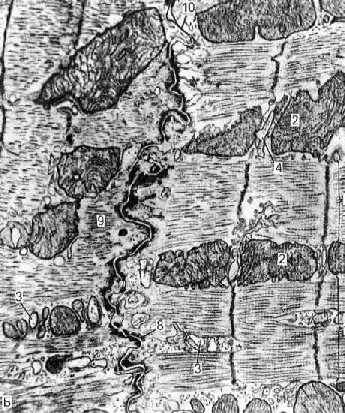

IV. Субмикроскопическое строение: микрофотография

| Электронная микрофотография - вставочный диск между кардиомиоцитами. 1. а) Наконец, от схемы перейдём к реальной электронограмме. | |

б) На снимке - крупным планом область вставочного диска.

в) Собственно граница между двумя кардиомиоцитами имеет вид

двойной извилистой линии, идущей посередине снимка сверху вниз.

2. Вновь можно указать

на два вида межклеточных контактов - щелевые контакты (10; в самом верху снимка) и многочисленные десмосомы (8; узнаваемые по утолщениям плазмолемм),

а также на место (9) прикрепления миофибрилл к плазмолемме.

3. а) Снимок подтверждает также, что

значительную часть объёма кардиомиоцитов занимают миофибриллы (светлые толстые полосы, идущие горизонтально).

б) Они "рассекаются" Z-линиями (идущими вертикально) на саркомеры.

4. а) Видны также

митохондрии (2), элементы L-системы (3) и Т-трубочки (4).